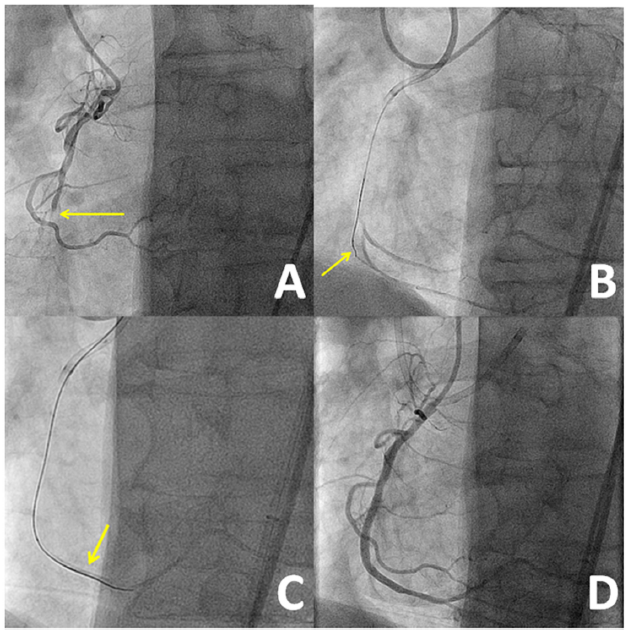

Case #2. A 69-year-old man with a prior history of hypertension, hyperlipidemia, nicotine dependence, and coronary artery disease presented with CCS class III angina on maximal medical therapy and adequate rate-pressure product control. He had undergone stenting of the LAD 7 years prior to presentation. Coronary angiogram demonstrated an RCACTO (Figure 3A) with a patent LAD stent.

Bilateral femoral arterial access was obtained with 45 cm-long, 8 Fr sheaths. The RCA was engaged with an AL 0.75 guide and the left main with an XB 3.5 guide. Given a tapered proximal cap and short lesion length with an angiographically visible microchannel (Figure 3A), a primary antegrade approach was pursued. An initial attempt at antegrade crossing using Fielder-XT (Asahi Intecc) and Pilot 200 guidewires was unsuccessful (Figure 3B). A brief attempt at retrograde crossing through septal perforators with a Sion guidewire also failed. A repeat antegrade crossing attempt with a Pilot 200 guidewire resulted in subintimal crossing. Dedicated reentry equipment (Stingray balloon and guidewire [Boston Scientific]) was unavailable, and wire-based reentry attempts with Pilot 200, Fielder XT, and Confianza Pro 12 guidewires were unsuccessful. A Gaia Third guidewire was successfully used for true lumen reentry, as confirmed by contralateral injection (Figure 3C). The RCA was stented with three drug-eluting stents with an excellent final angiographic result (Figure 3D). The patient had an uneventful recovery with complete resolution of angina.